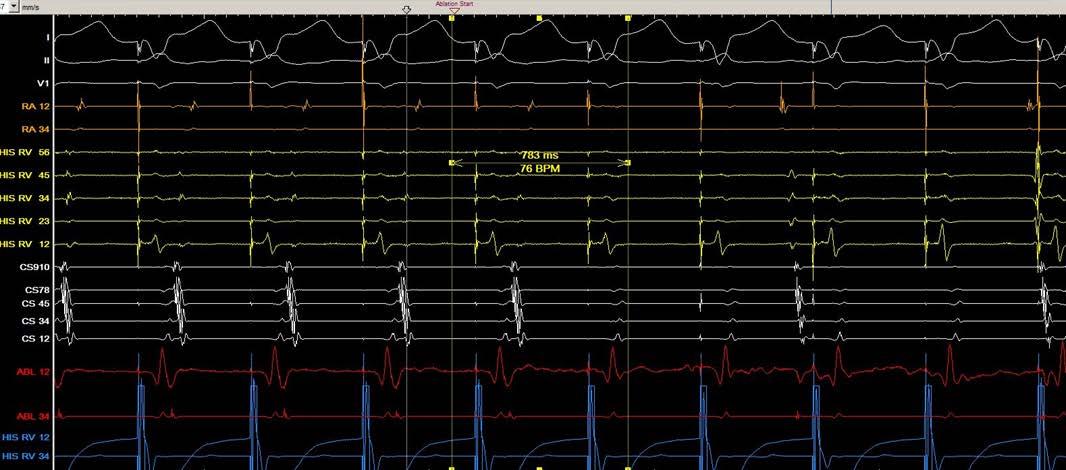

急診室, 3 歲時發作的 12 導程心電圖為 short RP narrow QRS tachycardia ( 圖一、發作時 ) ,因 RP interval 為 120 ms,orthodromic AVRT的可能性較大,retrograde P wave 的型態為I: +/-, II/III/aVF: -, V1: +,delta RP interval of III and V1: 0 ms ,根據 Tai et al. 的研究可以推論可能是 concealed posterior septal accessory pathway(1)。使用 adenosine後,tachycardia可以被矯正回sinus rhythm (圖 二、沒發作時 ) 。自出生後就一直服用 betablocker ,但 仍時常發作,因此在 13 歲時,我們安排了心導管電生 理檢查, RV burst pacing 時最早的 retrograde atrial activation是CS ostium,PAC時會誘發tachycardia (TCL: 446 ms) with the same retrograde atrial activation (concentric) when RV burst pacing (圖三),Ventricular overdrive pacing during tachycardia呈現VAV response with SA-VA of 48 ms and PPI-TCL of 72 ms (圖四),在 VOP 時 fusion beat can reset the next A ( 圖五 ) , Hisrefractory VPC can reset the next A (圖六),在tachycardia 時有出現RBBB pattern也沒有延長TCL (圖七),Antegrade conduction 經由 fast AVN ,綜合以上判斷 orthodromic

(圖三)、PAC induced tachycardia

(圖四)、Ventricular overdrive pacing during tachycardia

(圖五)、VOP reset the next A during fusion beat